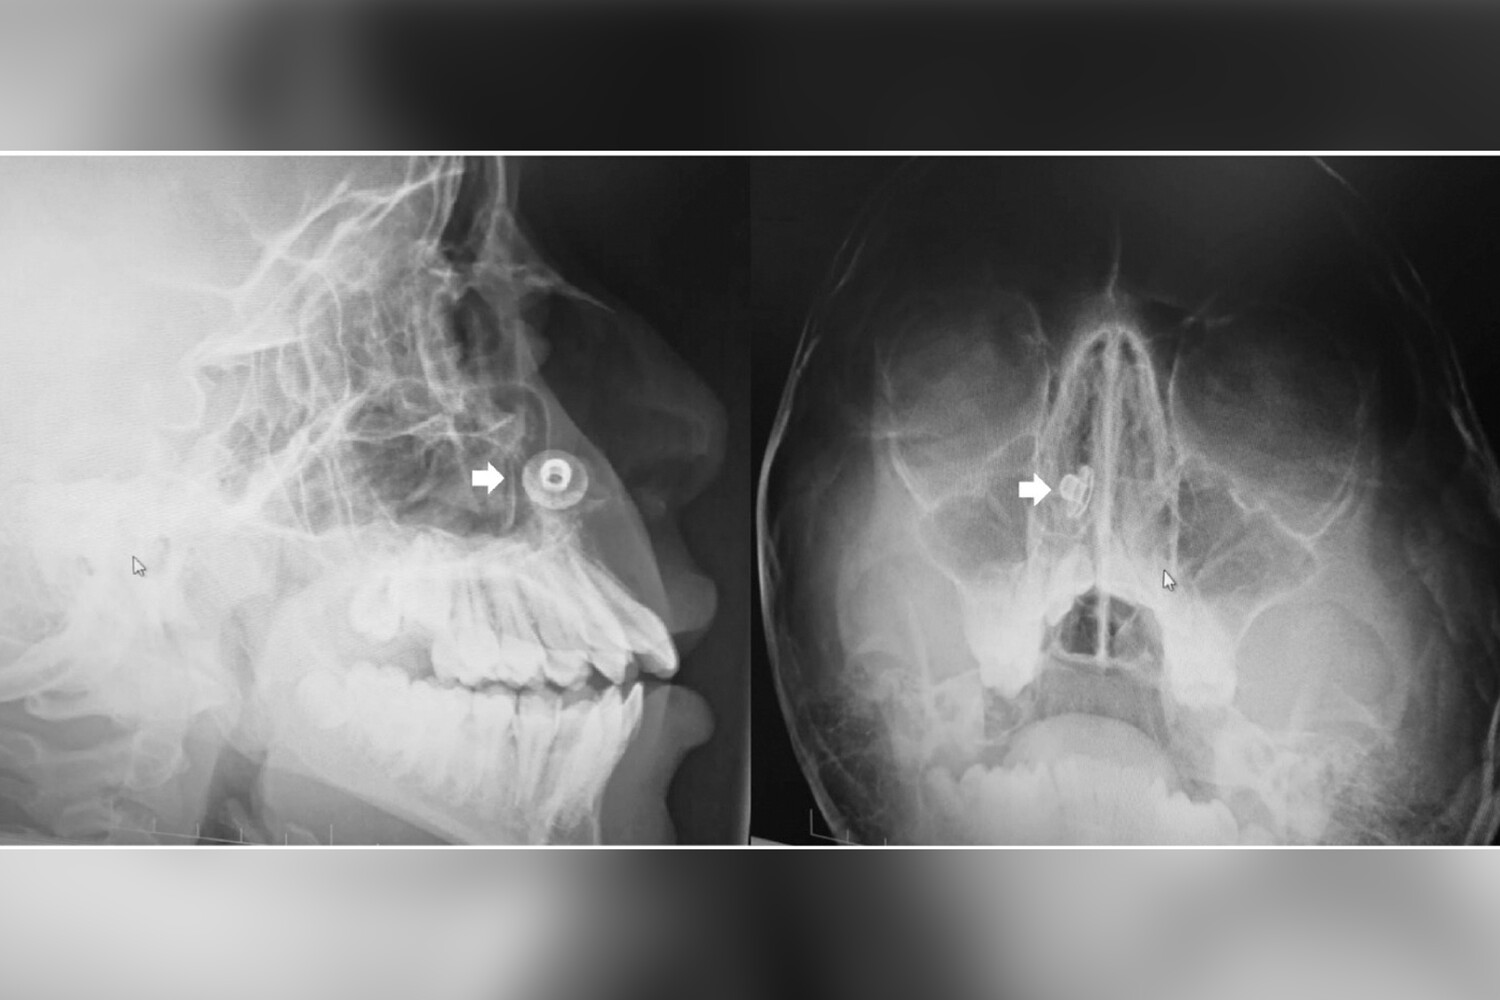

В носу 17-летнего подростка из Великобритании нашли металлическую пуговицу, которая находилась там 10 лет. Как сообщает Need To Know,

Недавно юноша пришел на плановую рентгенографию зубов, и во время процедуры медики обнаружили в нижней части его носовой полости инородный предмет. Подросток был потрясен, узнав об этом, и отрицал, что в детстве у него что-либо застревало в носу. Однако родители мальчика вспомнили, что обращались за медицинской помощью в связи с подозрением на инородное тело в носу, когда их сыну было семь лет.

Врачи объяснили отсутствие у пациента каких-либо симптомов, включая неприятный запах и насморк, удачным расположением пуговицы. В итоге ее удалили под местной анестезией, пока юноша находился в полусидячем положении, чтобы снизить риск смещения в дыхательные пути, добавили медики. После операции подростку прописали раствор, способствующий процессу заживления. За две недели он полностью восстановился и заявил, что чувствует себя хорошо.